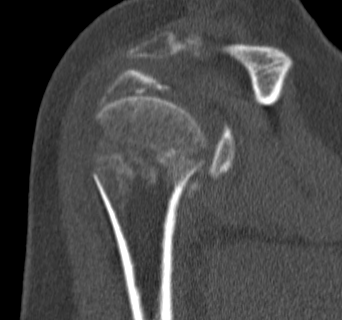

proximal humerus fracture Background ORIF with locking plate Arthroplasty Greater tuberosity fractures Lesser tuberosity fractures / avulsions Book traversal links for Proximal humerus fractures ‹ Pectoralis Major Tears Up Background ›